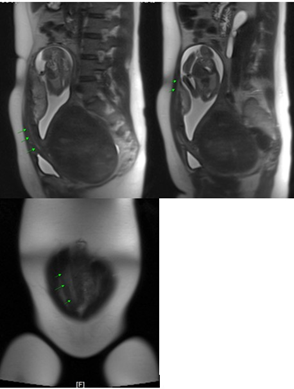

An MRI-scan was initiated due to these findings for appropriate planning of delivery. The MRI scan was performed at 20 weeks of gestation. The magnetic resonance imaging confirmed the suspected sacculation of the uterus due to a large fundal myoma of approximately 14cm in diameter. Furthermore, placenta praevia was diagnosed. Both maternal kidneys showed mild hydronephrosis. Overall, the patient was diagnosed with uterine sacculation due to a retroverted uterus caused by a fundal myoma (Figure 2).

Figure 2: The arrows show the elongated cervix in the MRI scan, sagittal view (picture above), coronal view (picture below)